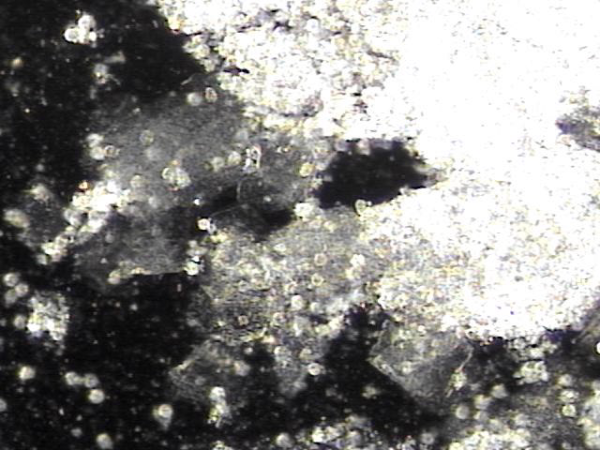

주2회 전립선의 표적 치료후 탈락된 상피세포 덩어리와 염증세포들입니다.

"Desquamated epithelial cell clusters and inflammatory cells after twice-weekly targeted prostate therapy."

주 1회 치료중 정낭에서 생산되는 염증 즉 프로스타그란딘 R로 생긴 염증 덩어리와 탈락된 거짓 중층 원주 상피세포의 치료된 현미경 학적 자료입니다.

This microscopic image shows the treated tissue from the seminal vesicles. It includes inflammatory clumps caused by prostaglandin-related inflammation, along with shed epithelial cells that had been blocking the ducts. These findings show that the treatment is helping to clear away these causes and improve circulation.

This microscopic image shows the resolution of inflammatory clusters, caused by prostaglandin R produced in the seminal vesicles, along with shed pseudostratified columnar epithelial cells, following once- or twice-weekly treatment.